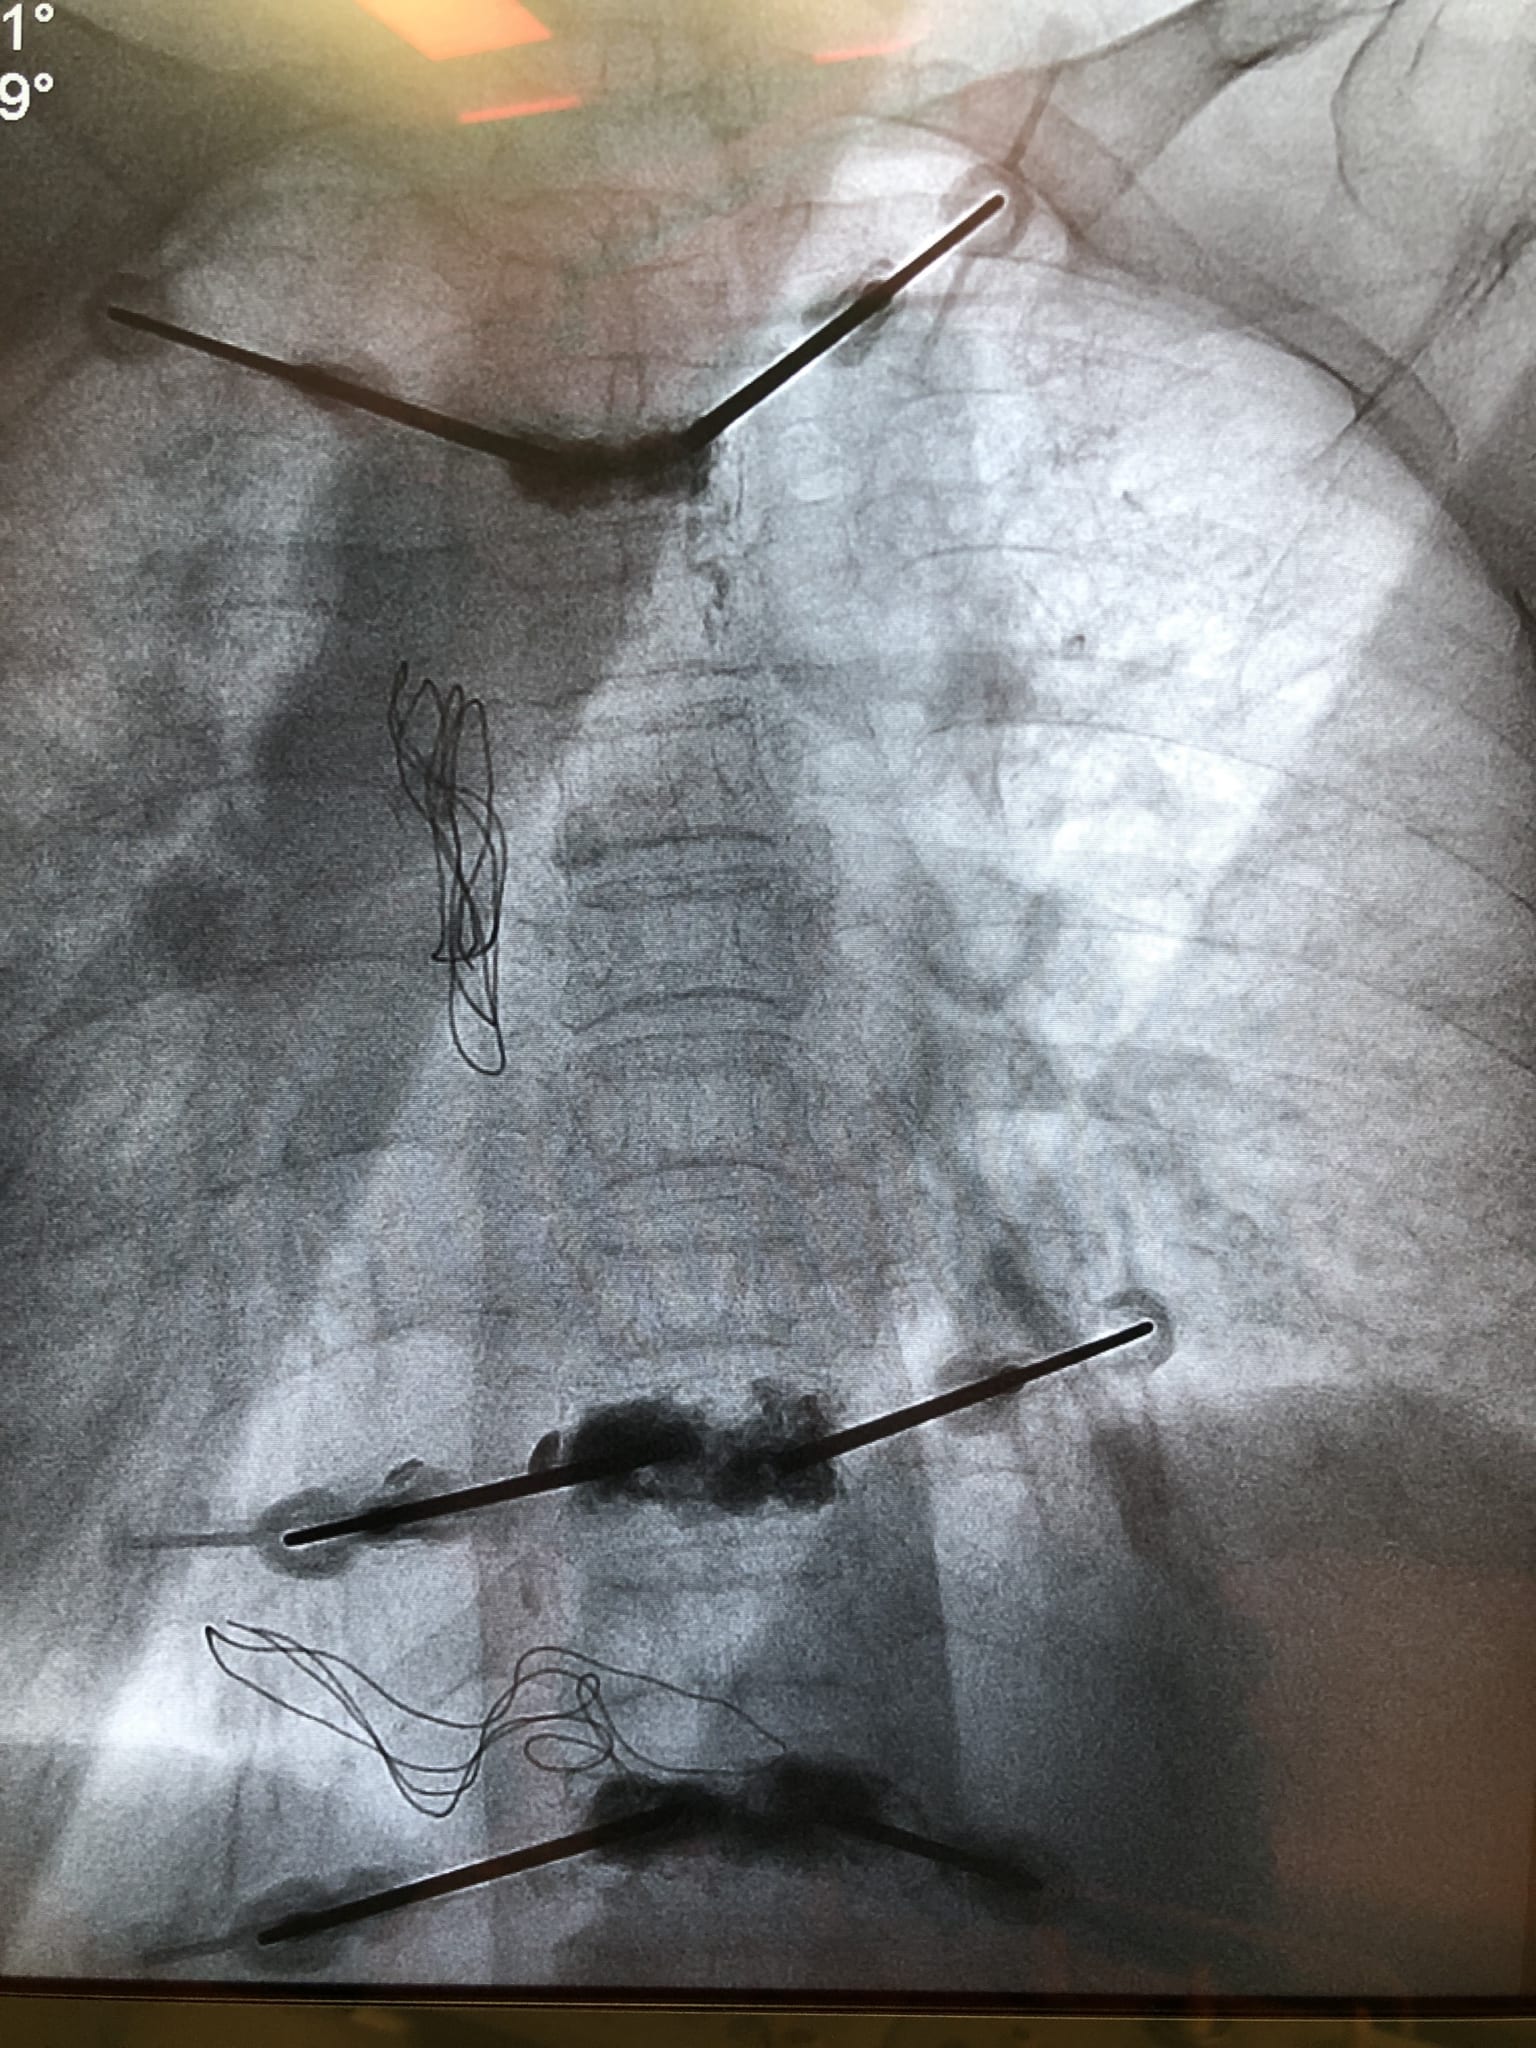

Với phát hiện này, đội ngũ chuyên gia, bác sĩ Khoa Ngoại chấn thương chỉnh hình của Bệnh viện đã nhanh chóng tiến hành hội chẩn và đưa ra phương pháp điều trị tốt nhất cho người bệnh đó là: Phẫu thuật tạo hình thân đốt sống D3,9,11 bằng bơm cement sinh học không bóng. Đến ngày 15/5, dưới sự hỗ trợ của hệ thống máy chụp số hóa xóa nền (DSA), ekip phẫu thuật đã thực hiện việc bơm xi măng sinh học dạng lỏng vào các đốt sống gãy để hàn gắn, kết nối các mảnh gãy lại với nhau, giải quyết việc xô lệch các mảnh gãy gây đau đớn cho người bệnh. Ca phẫu thuật thành công tốt đẹp, sau phẫu thuật cột sống của bệnh nhân đỡ đau nhiều và có thể ngồi dậy, đi lại ngay ngày thứ nhất.

Đánh giá về ca bệnh, BSCK1 Nguyễn Mạnh Thuần – Phẫu thuật viên chính của ca phẫu thuật cho biết: Đây là một phẫu thuật khó vì đường vào thân đốt sống D3 rất nhỏ nên có thể xảy ra nhiều nguy cơ tai biến như: Tổn thương tủy sống, mạch máu, thần kinh, phổi… gây hậu quả nghiêm trọng. Tuy nhiên, cùng với việc thường xuyên cập nhật, nâng cao trình độ chuyên môn kết hợp với sự hỗ trợ của trang thiết bị hiện đại nhất do Bệnh viện trang bị, đội ngũ chuyên gia, bác sĩ Bệnh viện đa khoa Quốc tế Hải Phòng đã và đang thực hiện rất tốt kỹ thuật tạo hình thân đốt sống bằng bơm cement sinh học, ngay cả với những ca bệnh phức tạp, giúp mang lại hiệu quả điều trị cao cho người bệnh. Phương pháp này ít xâm lấn, giảm đau nhanh, thời gian nằm viện ngắn. Đặc biệt, đối với các trường hợp gãy xẹp đốt sống do loãng xương hay chấn thương thì đây chính là giải pháp hiệu quả nhất, giúp người bệnh nhanh hồi phục, sớm quay trở lại với sinh hoạt bình thường.